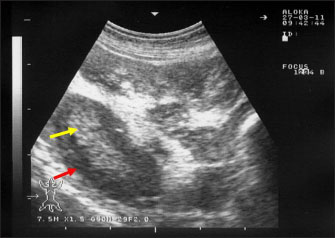

Ultrasonography has been proven effective for the early detection of several abdominal and thoracic disorders in small ruminants (Tharwat et al., 2012b; Tharwat and Al-Sobayil, 2017; Tharwat, 2021; Sadan et al., 2023; Tharwat and Al-Hawas, 2024a,b; Tharwat et al., 2024; Tharwat et al., 2025b). Recently, the technique has been found valuable for the diagnosis of various bacterial and parasitic infections in ruminants (Tharwat and Tsuka, 2024). An overall increase in intestinal mucosa thickness was detected in goats with PTB. It was classified as either mild, moderate, or severe (Fig. 2). Corrugation and folding of the intestinal mucosa may be also imaged in goats with PTB (Fig. 3). However, remarkable enlargement of the mesenteric lymph nodes are the most important findings in goats with PTB (Fig. 4). Other sonographic changes included increased hepatic brightness, intestinal edema consolidated lungs, and pleural, peritoneal, and pericardial effusions (Tharwat et al., 2012b).

Fig. 4. Ultrasonography of the enlarged mesenteric lymph nodes in a goat with paratuberculosis. The enlarged lymph node showed a hypoechoic cortex (red arrow) and a hyperechoic medulla (yellow arrow).